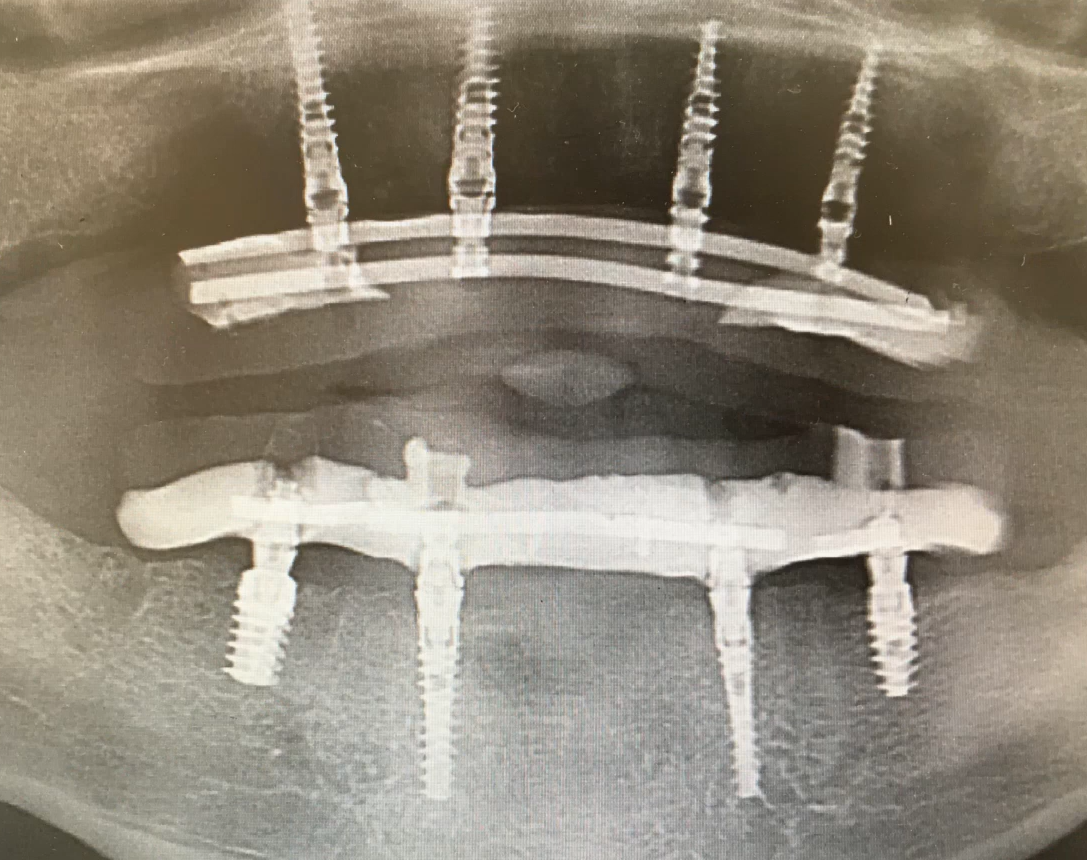

Each clinical case is individual, but there is a general pattern, as shown in the image below. Here, six implants were placed in the maxilla and four in the mandible.

An example of restoration of both dental arches: the dentures are reinforced, the maxilla has 6 implants for better load distribution in the loose bone, the mandible has 4 implants, which is sufficient, since the mandible bone is denser. YouTube/ Dr. Sergey Rozhnov /sergiodontologist

Such decisions are based on the fact that the bone tissue of the maxilla is not as dense as that of the mandible. Often, even in the anterior region, the density is D3, while in the posterior region, it is D4. However, proper selection of implant length, thread aggressiveness, and angled placement of distal implants allows for the creation of a stable structure even with four implants. We will discuss the selection of the number of implant lengths and diameters in more detail in the next part of this series.